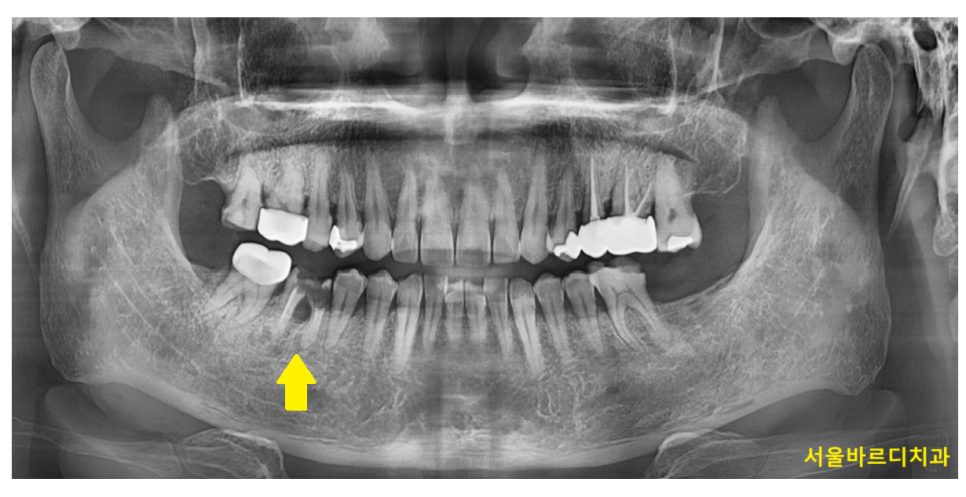

250124 치아 머리 부분에만 문제가 있고 잇몸 부위는 양호한 경우

250214 x-ray 검사로 임플란트 식립 시기 확인할 수 있습니다.

250408 뼈가 많이 녹은 경우 임플란트를 바로 심을 수 없습니다.

임플란트 식립 시기는 x-ray, ct등을 통해 결정됩니다.

보이지 않는 잇몸 내부안에 잇몸 뼈의 양과 질

염증 유무, 상태 등을 자세하게 관찰 할 수 있는 것이 x-ray입니다.